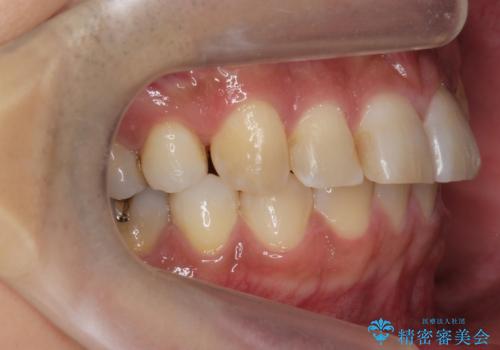

上の前歯が斜めに見えること、犬歯と小臼歯の間の隙間、上下顎前歯のがたつきを治すことをご希望されていました。

矯正期間(マウスピースを装着した期間):3ヶ月2週間(マウスピース14枚、1週間交換)

実際の矯正期間は3ヶ月2週間(マウスピース14枚、1週間交換)と短期間で治療を終えることができました。